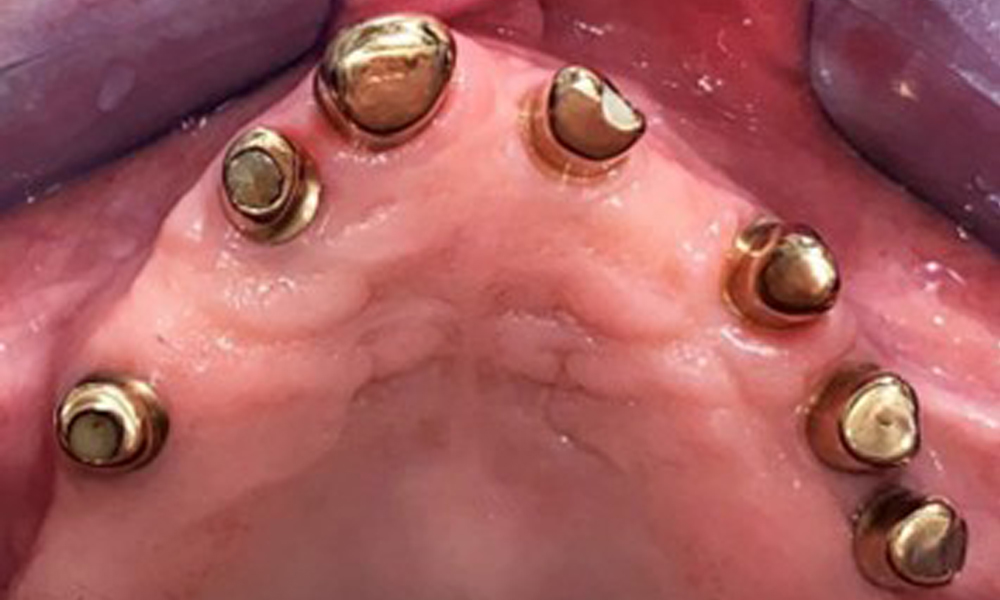

Occlusal view: Maxilla with tooth and implant-supported telescopic prostheses.

Fig. 2: Occlusal view: Maxilla with tooth and implant-supported telescopic prostheses

The patient was fitted with a combined removable maxillary telescopic prosthesis more than 25 years ago (Fig. 1, Fig. 2, Fig. 3) and is very happy with her dentures. The patient has an adequate fixed denture for the mandible (Fig. 4).

The dental findings are as follows: Combined removable implant and tooth-supported telescopic prostheses on implants 15, 13, 21, 23, 24, 25 and tooth 11 (Fig. 1, Fig. 2, Fig. 3). The patient was fitted with a fixed mandibular denture. Adequate bridges were present over 37 to 34 and 45 to 47 (Fig. 4), the crown margins were intact and there were no active caries. A composite filling with a marginal gap was present on tooth 43. There was mandibular gingival recession, exposing 1 to 3 mm of root surface. This also applies to 11.